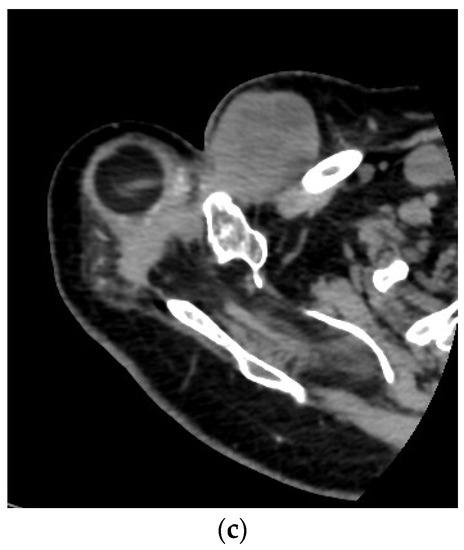

Figure 3.

A 71-year-old female patient underwent en bloc resection and reconstruction with a prosthesis for a bone giant cell tumor of the proximal humerus with a pathological fracture at presentation. Six months postoperatively, she experienced local recurrence and was treated with denosumab for 2 years and 5 months (a). She then underwent tumor resection and revision of prosthesis (b). One year after the revision, she experienced local re-recurrence and underwent tumor resection. One month later, a third local recurrence and lung metastasis were detected, and the biopsy revealed malignant transformation (c). She died of the disease 6 years and 4 months after the first surgery (Case 26, Table 3 and Table 4).